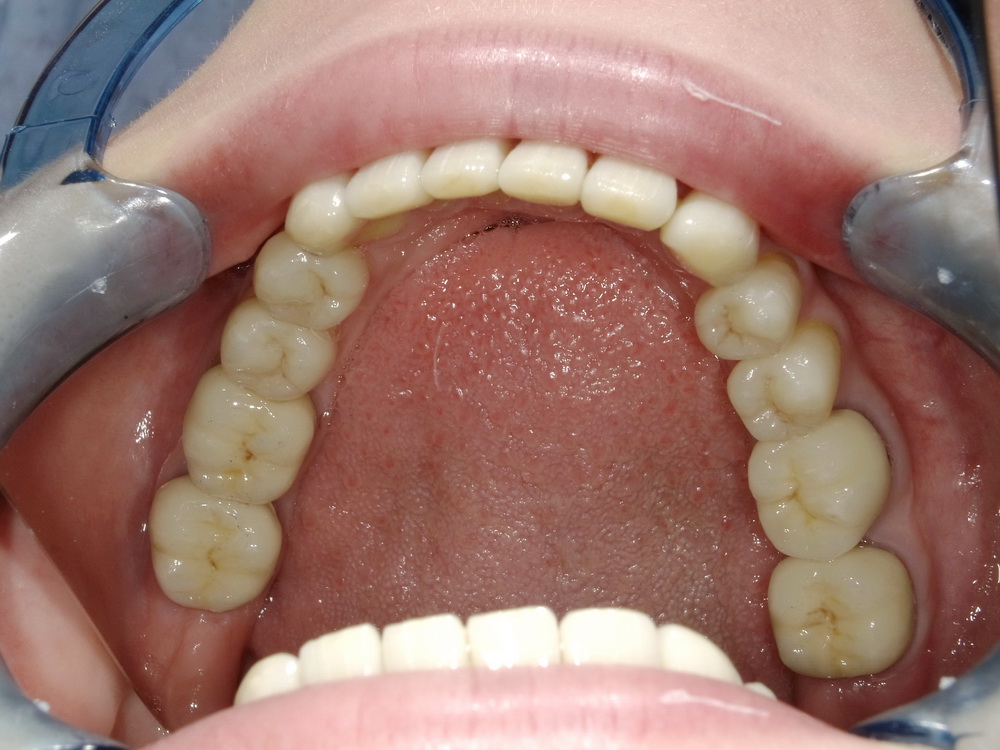

Totalrekonstruierte CMD-Patientin aus dem Münsterland zum Abschlussbefund

Die Patientin ist praktisch beschwerdefrei: 0-1.

Die Behandlung wurde mit Erfolg abgeschlossen, die Patienitn aufwändig instruiert.